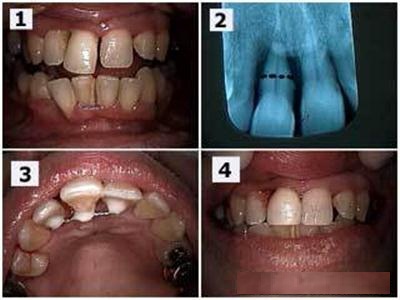

Treatment Of Badly Broken Tooth

Don't worry if you can’t find the fragment, your dentist will be able to use a tooth-coloured filling material to build your tooth up. If part of a back tooth is broken, it may either need a filling or a crown (also known as a cap).

If the tooth is badly broken and the nerves are exposed, it may be a little sensitive and may even need root canal treatment. This involves removing the nerve and placing a root filling.